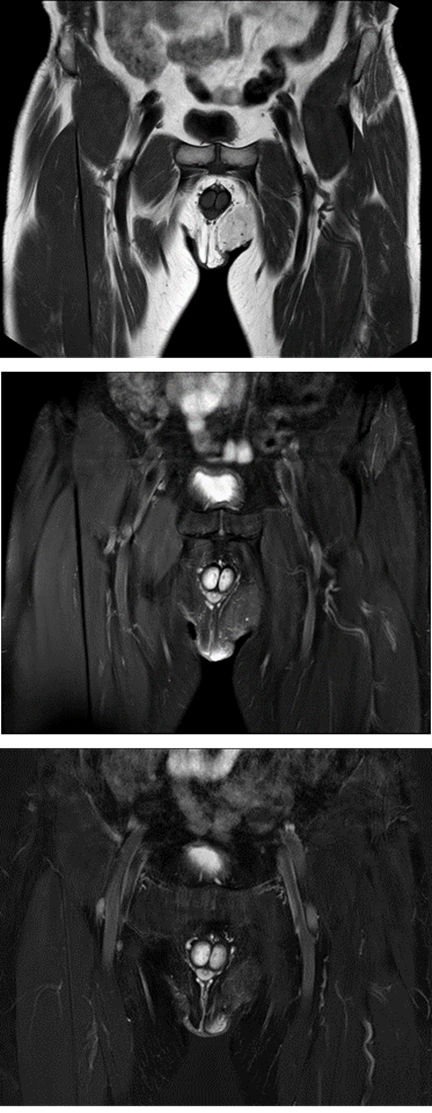

Para su mejor caracterización fue practicada una resonancia magnética (RM), visualizándose la tumoración descrita levemente hipointensa en T1 con respecto a la grasa locorregional, con contenido graso en su interior, aunque sin suprimirlo completamente en secuencia selectiva SPAIR pero sí en la DIXON (Figura 2), planteando el diagnóstico radiológico de hibernoma como primera posibilidad. No se visualizaron adenopatías ni lesiones óseas.

Figura 2 RM. Primera imagen, secuencia T1 que muestra una lesión hipointensa con respecto a la grasa locorregional. En el centro, secuencia T2 con técnica de supresión grasa SPAIR con supresión incompleta del contenido graso. Última, secuencia T2 con técnica DIXON que suprime completamente la grasa lesional.